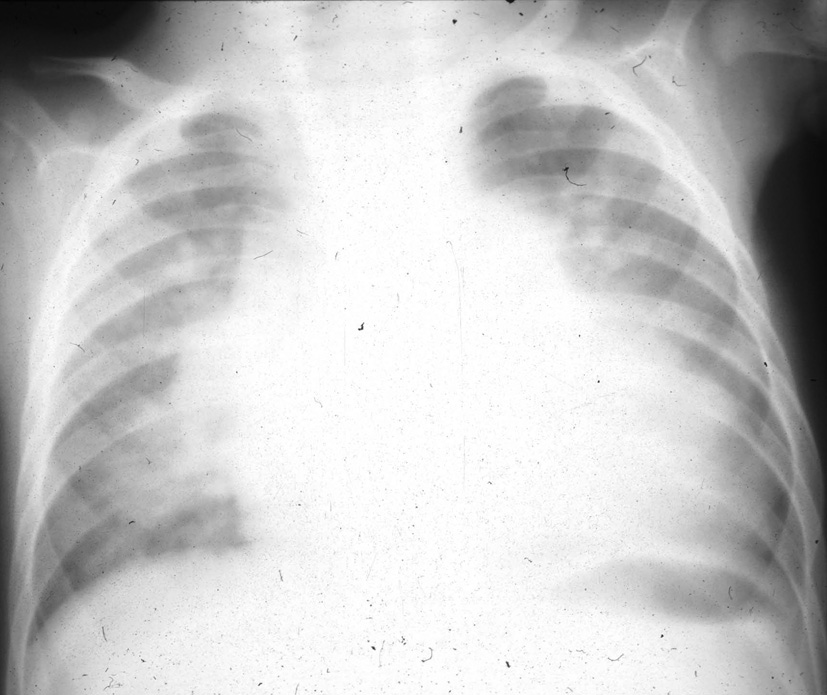

La coarctation préductale (c’est-à-dire située en amont de l’émergence du canal artériel ou ductus arteriosus), ou sténose de l’isthme de l’aorte, est une forme grave de la coarctation aortique, symptomatique dès les premiers jours de vie, mais les symptômes n’apparaissent qu’au moment de la fermeture du canal artériel. La chirurgie est urgente (figures 1 et 2).

Les cardiopathies complexes sont fréquentes, très polymorphes (ventricule unique, atrésie tricuspide, truncus arteriosus ou tronc artériel commun, etc.). Elles associent à des degrés divers cyanose et défaillance cardiaque suivant les cas (cf. figure 2).

- Risque d’hypertension artérielle pulmonaire (HTAP) irréversible si le shunt est opéré trop tard. Chirurgie en général dans la première année de vie (figures 3 et 4).